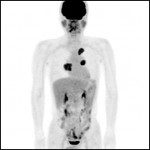

- PET-CT装置

PET-CTはがん細胞が正常細胞に比べ多量のぶどう糖を必要とする性質を利用してがんを発見します。1回の検査でほぼ全身を調べることができます。 -

画像診断部門では、エックス線、ガンマ線、磁気、超音波などを用いて様々な検査・診療用画像の提供を行っています。PET-CTは長野県南部において最初の導入施設であり、実績があります。地域医療連携係を通して広く検査を受け入れています。